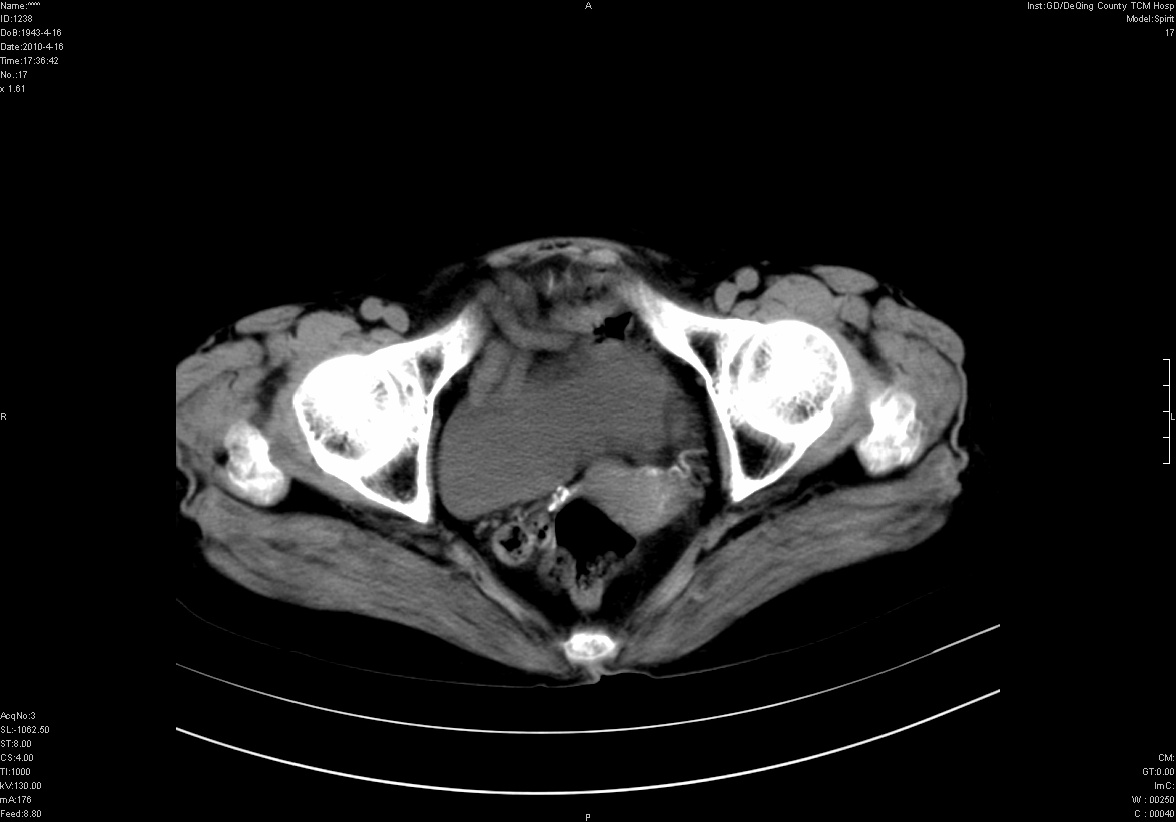

标题: CT25796:女,60岁,腹痛5天,请会诊??? [打印本页]

标题: CT25796:女,60岁,腹痛5天,请会诊???

考虑卵巢畸胎瘤。

支持右侧盆腔畸胎瘤。

畸胎瘤

右侧附件畸胎瘤

考虑右侧卵巢畸胎瘤。

考虑右侧卵巢畸胎瘤

右侧卵巢畸胎瘤可能。